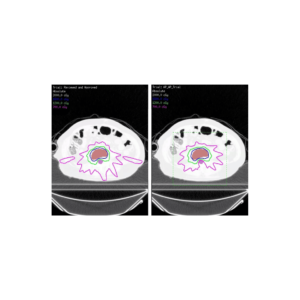

Функция Автоматического планирования оптимизирует объем исследуемого объекта и защиту чувствительных органов. Уменьшает необходимость многократной проверки плана врачом и дозиметристом и работает в фоновом режиме, освобождая время для других задач.